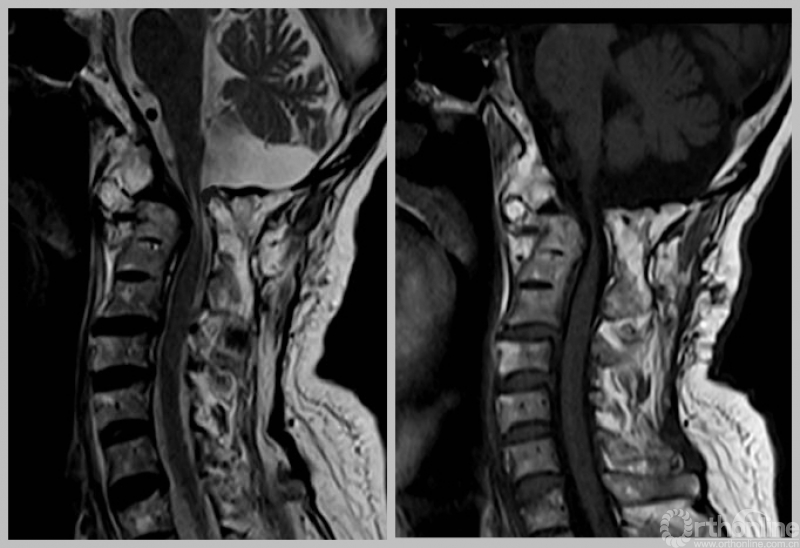

MRI

寰枢椎脱位或称为寰枢关节脱位,是指颈椎的第一节(寰椎)、第二节(枢椎)之间的关节失去正常的对合关系。这是一种少见但严重的疾患,其可以引起延髓、高位颈脊髓受压,严重者致四肢瘫痪、甚至呼吸衰竭而死亡。

1. 寰枢椎脱位

2. 枕颈融合术后

3. II型呼吸衰竭

4. 延髓麻痹?